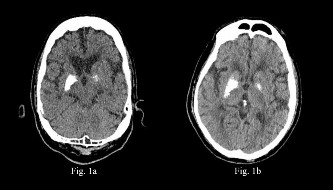

Se presenta el caso de un paciente de 75 años, con antecedentes de colecistectomía hace cinco años, diabetes mellitus tipo 2 e hipertensión arterial en tratamiento (insulina lispro, glargina y metformina para la primera e irbesartán y atorvastatina para la segunda), ambos seguidos de manera irregular por el paciente, además, recibe tamsulosina debido a una hiperplasia benigna de próstata y quetiapina más haloperidol por un cuadro de trastorno delirante esquizofreniforme aunado a un trastorno cognitivo leve desde hace tres años. En esa fecha se le realizó una tomografía cerebral sin contraste, en la que se apreciaron calcificaciones confluentes a nivel de los ganglios basales a predominio derecho, sin mayores comentarios sobre dichos hallazgos en su centro de atención (Figura 1a).

Por lo anterior, se interconsulta a gastroenterología. Cabe destacar que hasta ese momento el paciente no estuvo recibiendo medicación indicada por psiquiatría, lo que explica los sucesos del segundo día de internamiento: un episodio de agitación con subsecuente caída y posterior traumatismo craneoencefálico leve asociado a sensorio oscilante. Debido a ello, se le realiza una tomografía cerebral sin contraste para evaluar lesiones subsecuentes a la caída; de forma incidental encuentran prominentes calcificaciones confluentes a nivel de los ganglios basales derechos a predominio lenticular (Figura 1b), siendo dichos hallazgos, en el contexto del paciente, compatibles con enfermedad de Fahr.

Figura 1 1a. Tomografía cerebral sin contraste, con calcificaciones a nivel de ganglios basales, sin alguna apreciación al respecto en su centro de atención. 1b. Tomografía cerebral sin contraste, con calcificaciones confluentes a nivel de los ganglios basales a predominio derecho, que ya se observaban en un estudio previo.